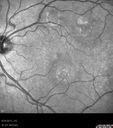

Cuticular Drusen (Basal Laminar Drusen) and Bilateral Chronic Subfoveal Fluid (Serous Retinal Detachment) unresponsive to monthly Avastin - Fundus Autofluorescence OD820 views66-year-old man with bilateral subfoveal fluid unresponsive to one year of monthly avastin therapy.

OD 20/160, Pinhole 20/80. OS 20/63, Pinhole 20/50. OCT scan shows subretinal fluid with normal choroidal thickness. Fluorescein angiogram shows cuticular/basal laminar drusen. ICG shows no foci of choriocapillaris leakage.